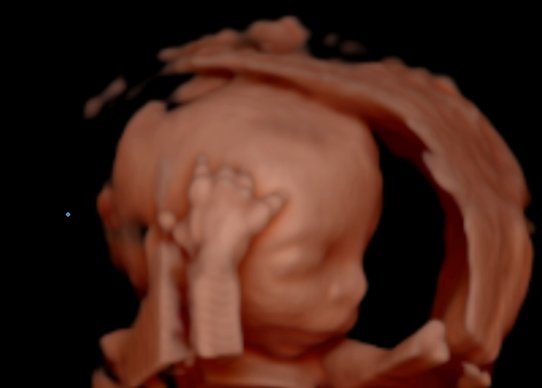

Co je 3D/4D ultrazvukové vyšetření a jaký je jeho klinický význam?

Troj-/čtyřrozměrné (3D/4D) ultrazvukové vyšetření je prostorovou rekonstrukcí vzhledu plodu, která umožňuje rodičům snadněji si vytvořit představu o morfologii obličeje a eventuálně i tělu plodu. Zatímco 3D vyšetření poskytuje pouze statický prostorový obraz plodu, 4D je dynamickým prostorovým obrazem zachycujícím plod v pohybu.

(Foto: MUDr. Veronika Frisová, Profema)

Pokud se těhotná žena sama cíleně objednává na 3D/4D ultrazvuk, jedná se o objednávku komerčního vyšetření, při kterém jsou pořízeny pěkné snímky obličeje plodu, eventuálně jeho celého těla. Obvykle je také připojen videozáznam na DVD. Ačkoli součástí 3D/4D ultrazvukového vyšetření je i orientační kontrola růstu plodu a jeho anatomie, toto vyšetření rozhodně neslouží k diagnostice výskytu vrozených vad. Těhotná žena musí naopak při 3D/4D ultrazvukovém vyšetření podepsat informovaný souhlas, že se nejedná o klinické vyšetření plodu za účelem záchytu vrozených vad.

Kromě komerčního využití lze 3D/4D ultrazvukové vyšetření cíleně připojit i k detailnímu genetickému ultrazvuku a zpřesnit jím tak efektivitu záchytu vrozených vad vybraných systémů plodu (především vyšetření mozku, páteře a rozštěpových vad obličeje). Tento typ 3D/4D ultrazvukového vyšetření tvoří v některých specializovaných centrech součást detailního genetického ultrazvuku. Jeho cílem není zobrazení povrchu obličeje plodu, ale především zpřesnění diagnostiky vrozených vad.